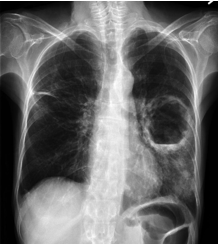

nhất là khi thay đổi tư thế và khạc mủ số lượng ít hơn. Xquang ngực trong giai

đoạn điển hình có thể cho thấy ổ mủ trong phổi rõ ràng với một hoặc nhiều hang

dạng tròn có mức nước - hơi, bờ dày, xung quanh là tổ chức phổi đông đặc do bị

viêm.